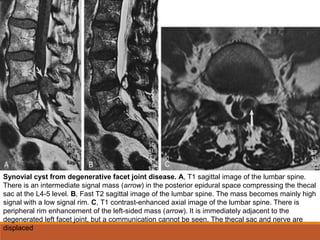

Synovial cyst from degenerative facet joint disease. A, T1 sagittal image of the lumbar spine.

There is an intermediate signal mass (arrow) in the posterior epidural space compressing the thecal

sac at the L4-5 level. B, Fast T2 sagittal image of the lumbar spine. The mass becomes mainly high

signal with a low signal rim. C, T1 contrast-enhanced axial image of the lumbar spine. There is

peripheral rim enhancement of the left-sided mass (arrow). It is immediately adjacent to the

degenerated left facet joint, but a communication cannot be seen. The thecal sac and nerve are

displaced

• 54.

Synovial cyst fromdegenerative facet joint disease. A, T1 sagittal image of the lumbar spine. There is an intermediate signal mass (arrow) in the posterior epidural space compressing the thecal sac at the L4-5 level. B, Fast T2 sagittal image of the lumbar spine. The mass becomes mainly high signal with a low signal rim. C, T1 contrast-enhanced axial image of the lumbar spine. There is peripheral rim enhancement of the left-sided mass (arrow). It is immediately adjacent to the degenerated left facet joint, but a communication cannot be seen. The thecal sac and nerve are displaced